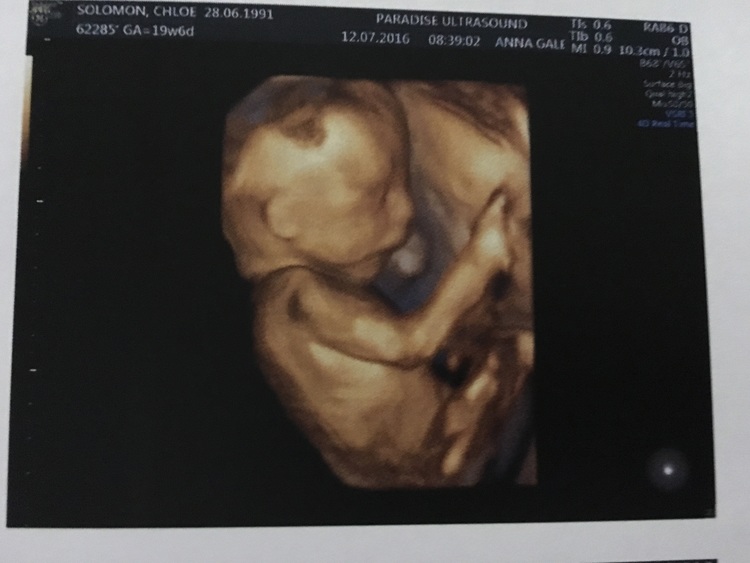

I’m going to be a big brother! July 19, 2016 Author: lancensolomon Woweee, in November i’m going to be a big brother. My little brother, Theodore Rex will be joining my sister and I. I cannot wait to play with him and show him all the cool things in the world 0 0 0 Share this:Click to share on Twitter (Opens in new window)Click to share on Facebook (Opens in new window)Like this:Like Loading...